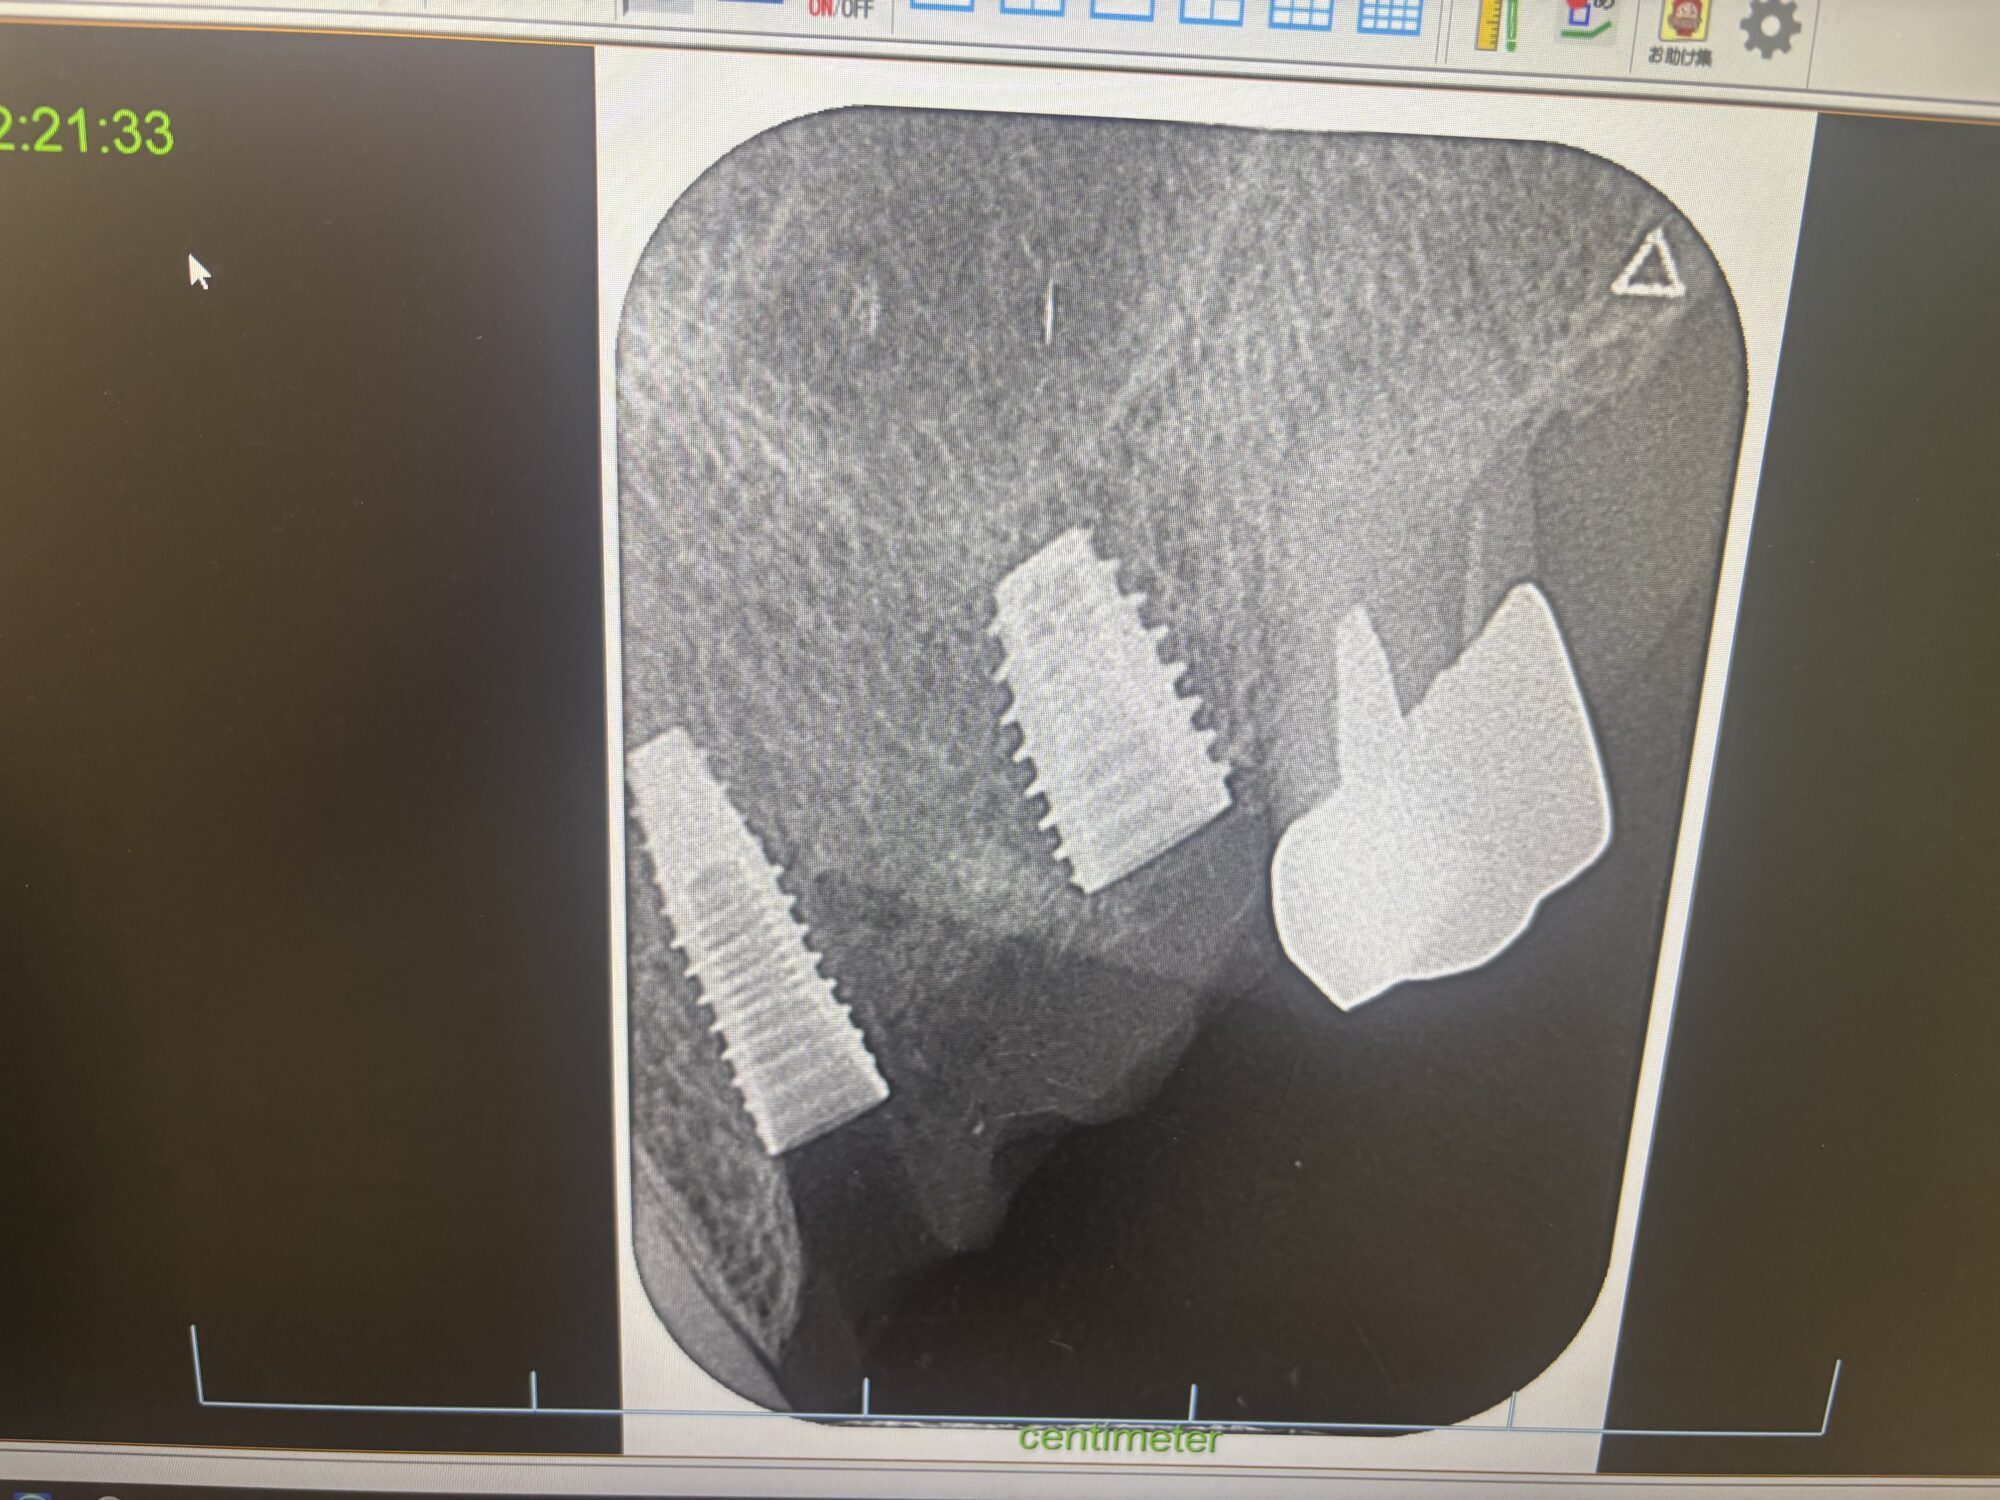

インプラント治療について 2025-09-26 こんにちは古賀歯科医院です。 当医院では、インプラントの治療を行っております。 インプラント治療は高額ですが、とても素晴らしい治療だと思います。 しかし、インプラントも天然の歯と同様に歯周病になります。 インプラントのメンテナンスは必ず行ってください。 インプラントの埋入や、メンテナンス、相談などお気軽にお問合せください。